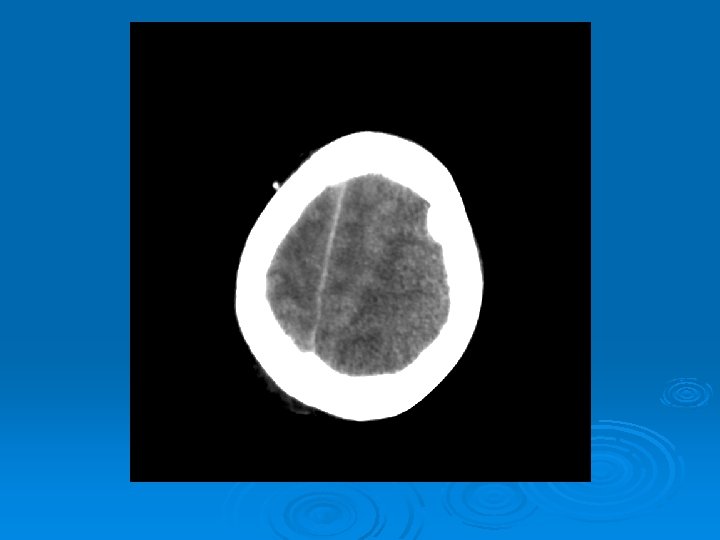

Course: Ø 3 PM, RN noticed anisocoria and L pupil non-reactive. Ø Neurology STAT dose mannitol and w/ dilantin. Ø Pt went for stat head Ct:

CT head 2/11/07 Ø A right frontal ventriculostomy catheter Ø Diffuse sulcal effacement with thickening of the cortex. Ø Loss of gray-white differentiation and hypodensity in the left parietooccipital region. Ø There is diffuse hypodensity of the cerebellum and brainstem. Ø Ø Ø The basilar cisterns are nearly completely effaced. Ø Impression: Ø Worsened diffuse cerebral edema The lateral ventricles are smaller

Course: Ø Neurosurgery saw pt: on exam she had lost cough, gag reflexes, corneal reflexes, she had flexed RUE, semipurposeful with bilateral extended LE. Ø Concern for herniation: placed Ø ICP 35 -40 10 th-11 th EVD